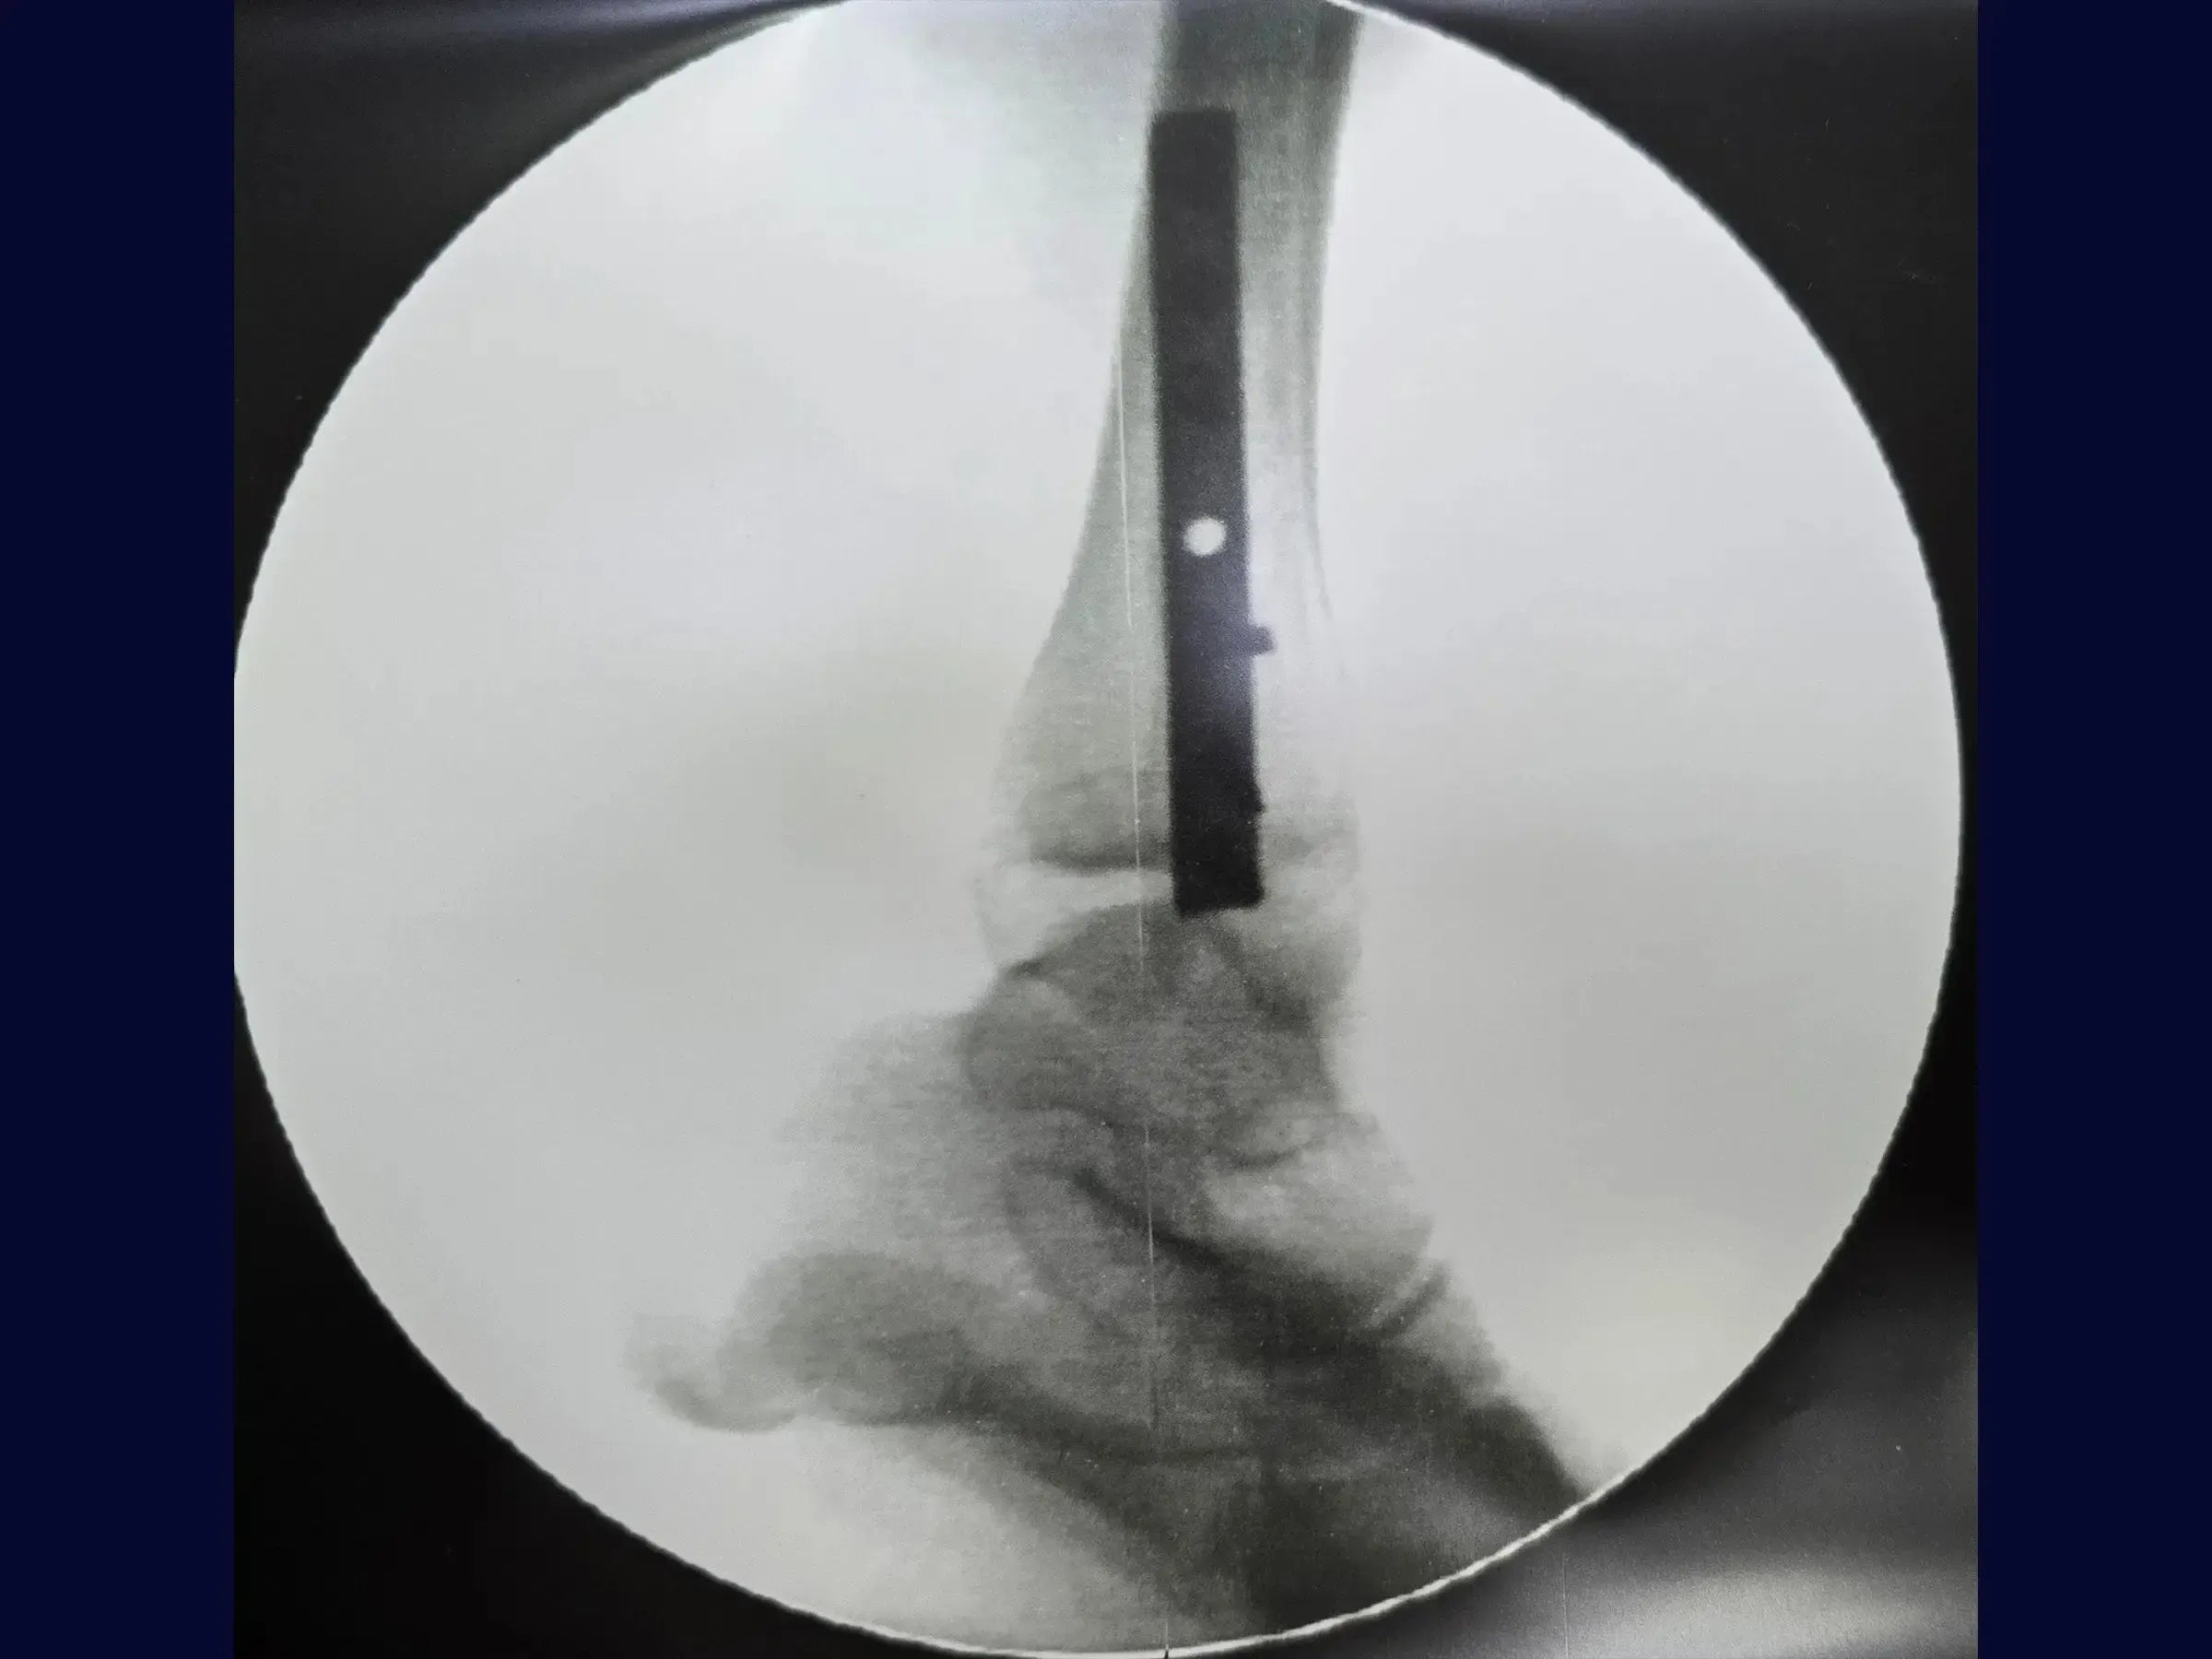

- Técnica de osteossíntese com placa posterior para controle do cisalhamento.

- Estratégia Adaptativa com Placa Posterior: Abordagem para gerenciar fraturas complexas e fragmentadas, garantindo estabilidade e redução.

- Fixação com Parafuso de Tração da Placa: Posicionamento estratégico do parafuso para estabilização da fratura através da compressão.

- Modelagem Distal da Placa: Prevenção de irritação de tendões fibulares, otimizando o conforto pós-operatório.

- Visualização Detalhada em 4K (Perspectiva Cirúrgica): Análise de alta resolução dos passos cirúrgicos com detalhes anatômicos e instrumentais.

- Análise Pós-Procedimento de Decisões Intraoperatórias: Compreensão crítica das escolhas cirúrgicas e seus fundamentos.